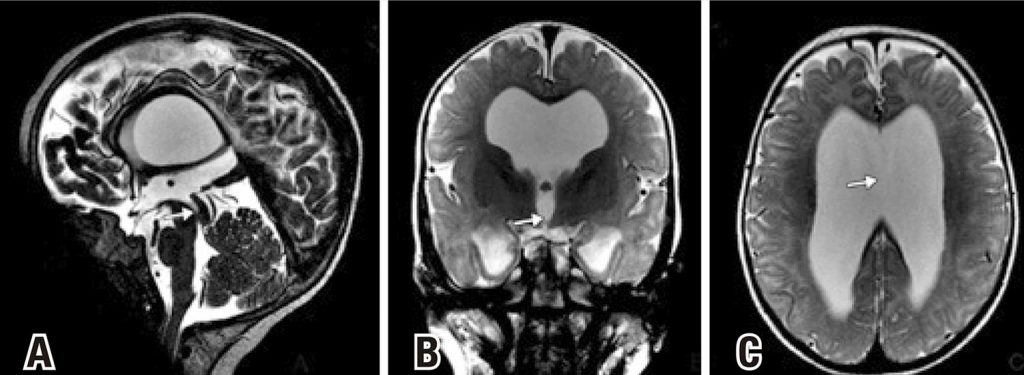

Chromosomal abnormalities are responsible for several congenital malformations in the world, some of these are associated to telomeric/subtelomeric deletions. The abnormalities involving the telomere of chromosome 12 are rare, with few reports of deletions involving 12q24.31 region in the literature, and, to our knowledge, only four of them in the 12q24.31-q24.33 region. We report a further case of interstitial deletion of bands 12q24.31-q24.33 associated with autism spectrum disorder. A 2-year-old boy with global developmental delay associated with multiple congenital anomalies. The Human Genome CGH Microarray 60K confirmed the diagnosis of 12q deletion syndrome. This study made a review of the current literature comparing our patient with previously reported cases. These detailed analyses contribute to the development of genotype/phenotype correlations for 12q deletions that will aid in better diagnosis and prognosis of this deletion.